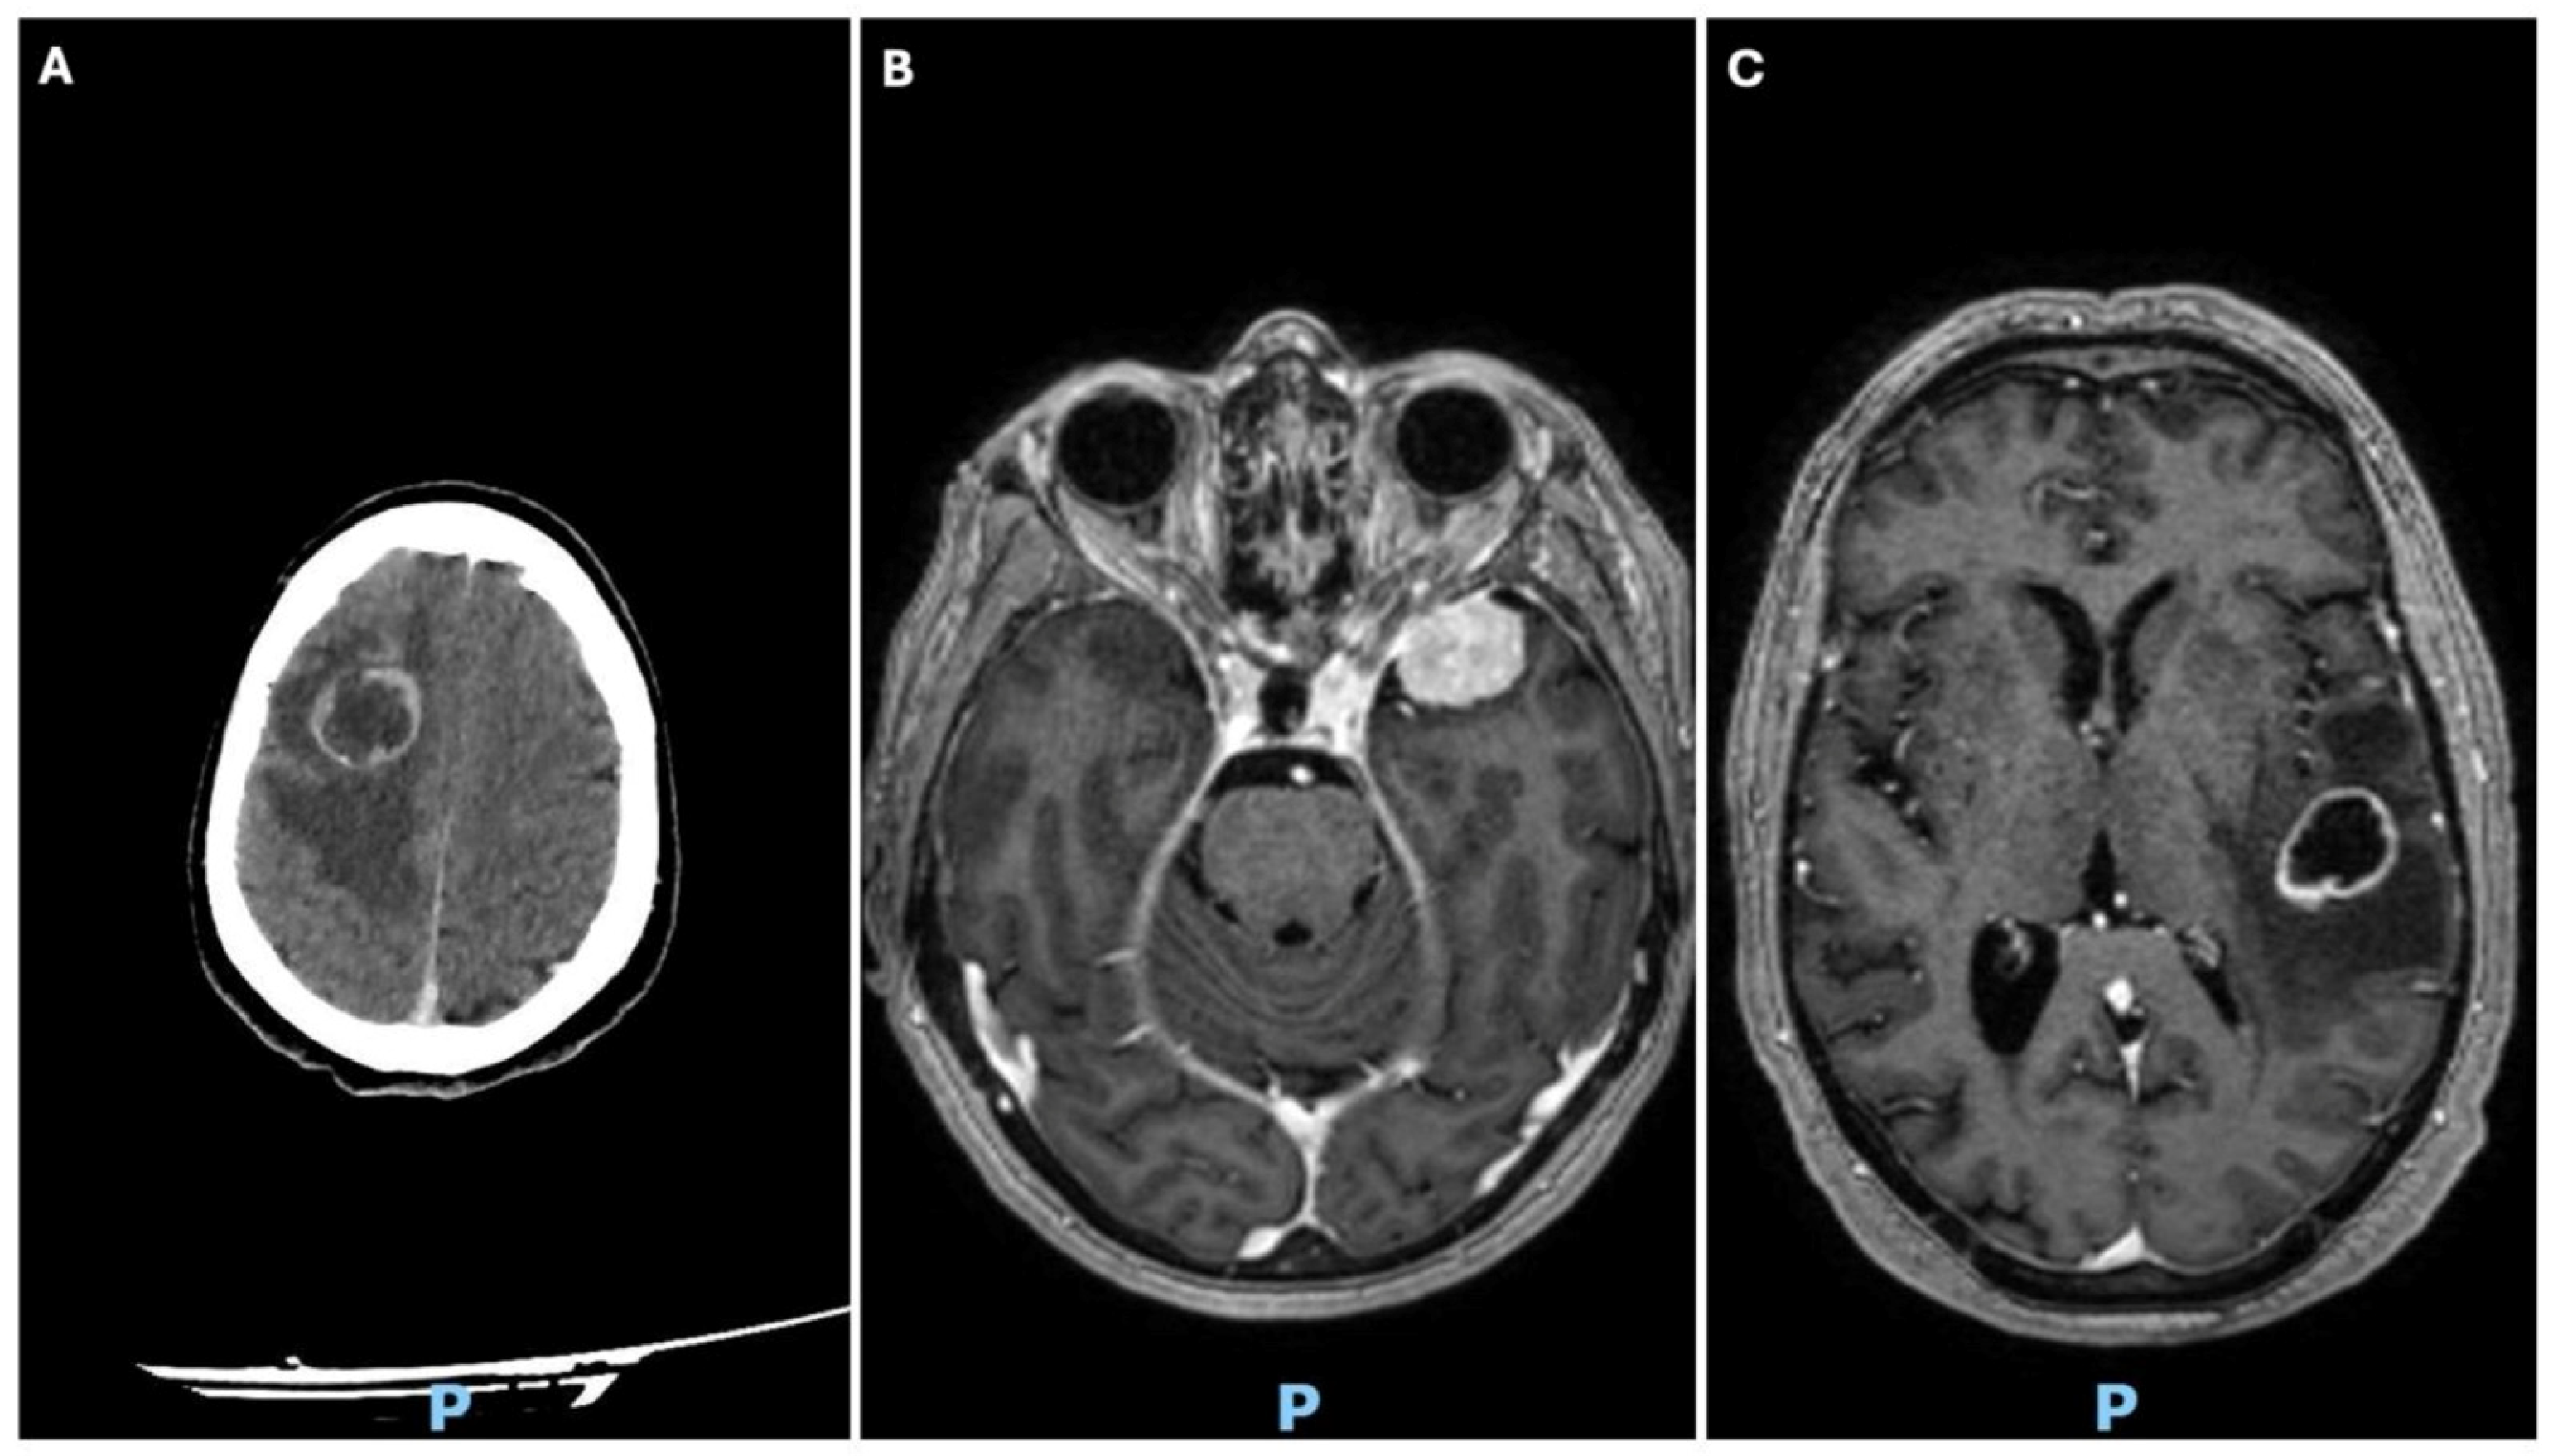

3.1. Case 1

3.2. Case 2

3.3. Case 3